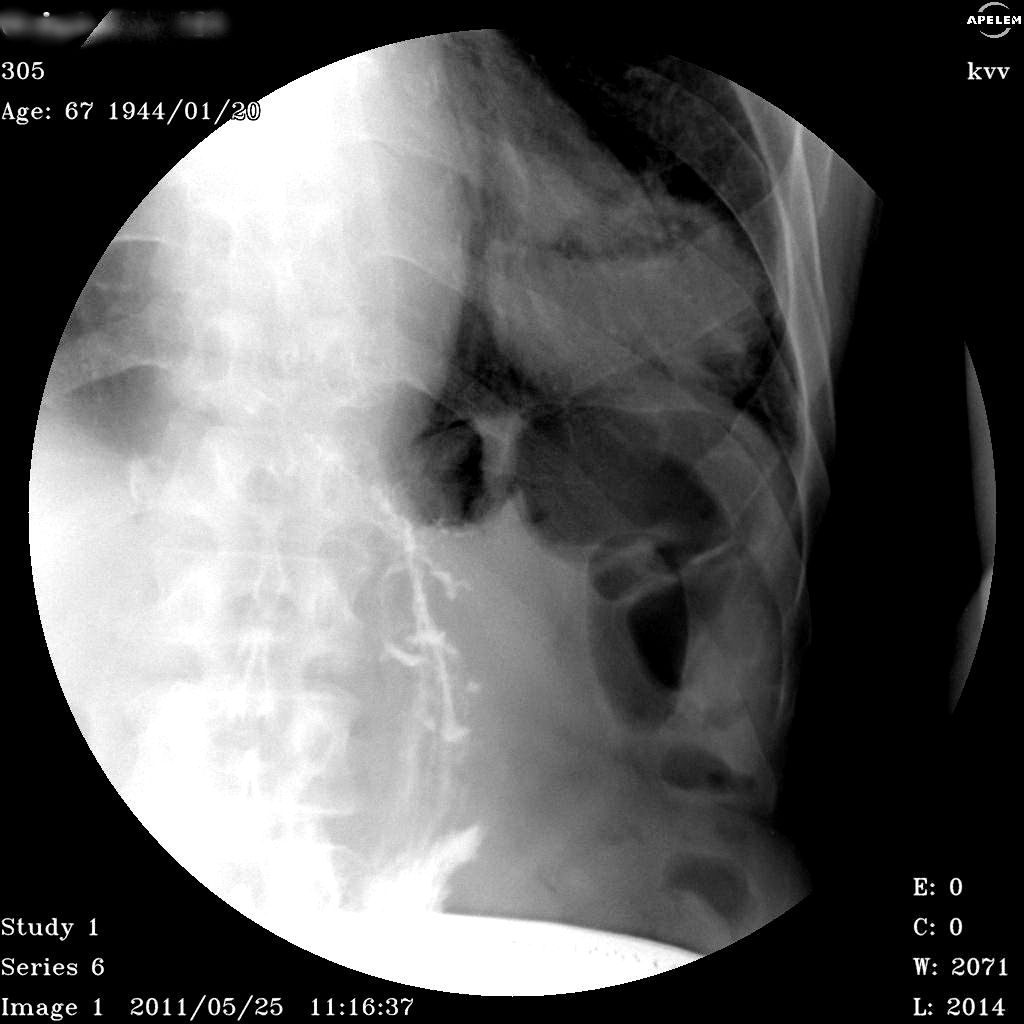

Поступил с Cr. языка. ОАК - Ле-11,0 СОЭ 40. Жалоб, как таковых нет. Кашель есть, но постоянный (много курит) Эпизодов поднятия температуры не было. Выполнили линейную томограмму стоя. В качестве одной из версий предположили необычную грыжу - дали барий.

Дренированный абсцесс, как мне кажется.

Тоже склоняюсь к частично дренированому абсцессу.

Конечно, стопроцентно исключить распадающийся рак мы не можем, равно как и первичную полостную форму рака, а то и распад в крупном метастазе рака языка (что никто и не отменял)....

имхо:По случаю, всё подробно изложил stovbav- дифференцировать дренированный абсцесс и опухоль ( первичную либо вторичную). Пределы возможностей классической рентгенологии, по этому случаю исчерпаны-показана КТ.